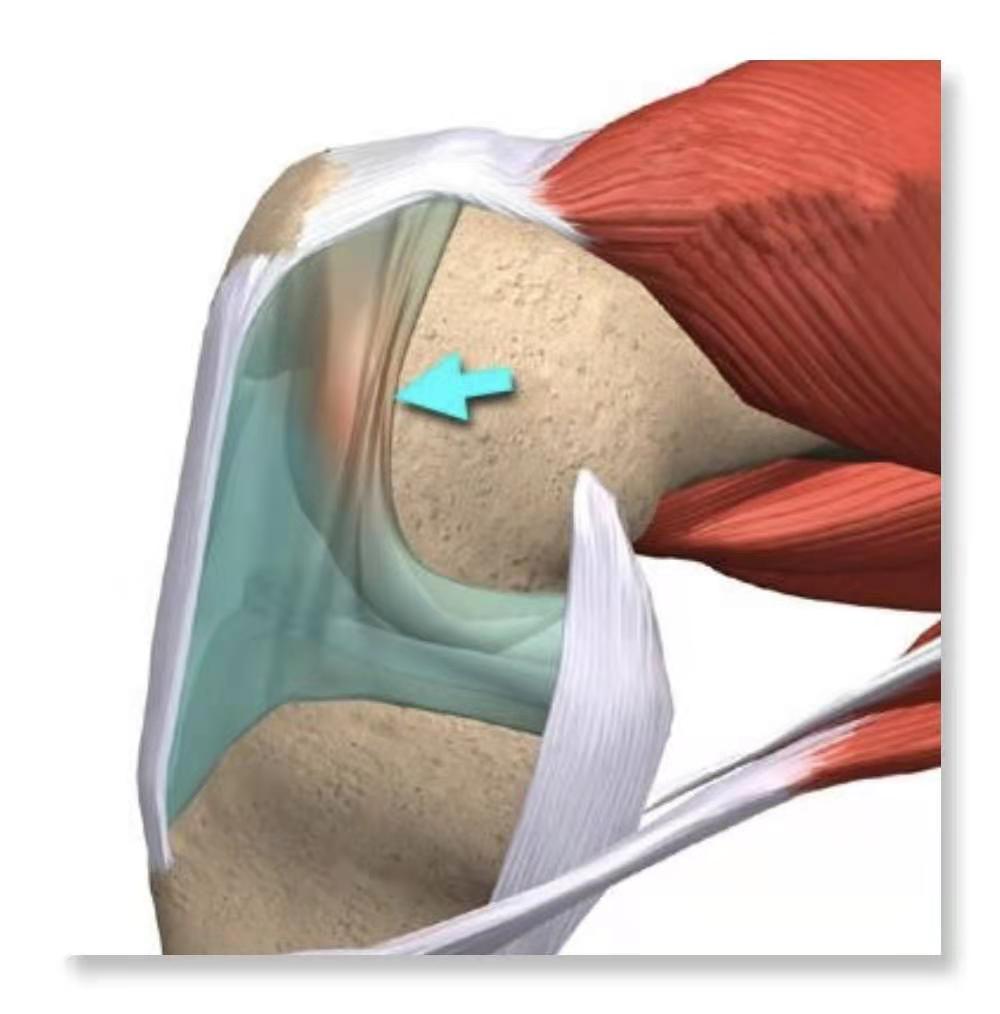

在关节镜出现之前,即使关节切开手术时医生发现这些像紧束带一样的“滑膜皱襞”,多理解为关节内黏连的结构予清除掉,没有“滑膜皱襞”的概念。其实滑膜皱襞是关节的正常结构,人群中有一定比例的人有这样的结构。没有发育异常或病变的皱襞是不会产生膝关节不适的症状的。膝关节内的滑膜皱襞包括:髌上皱襞、髌内侧皱襞、髌下中央襞、翼状皱襞等。其中容易产生症状的是:髌内侧皱襞。我们就来专门见见它的“庐山真面目”。

(此图来之互联网)

蓝色箭头所指的就是髌内侧滑膜皱襞。尽管不是所有人有这样的结构,它就是出现了,也是平贴在股骨内侧髁上,正常可活动的皱襞不会产生膝关节不适的症状。钝性创伤和反复在髌骨与股骨内髁卡压、嵌入等原因可以引起局部的滑膜炎与水肿,继而使这个结构产生纤维化并失去弹性。滑膜皱襞增厚不能弯曲时,就会出现疼痛与膝关节活动时伴声响,这时才能诊断“滑膜皱襞综合征”。